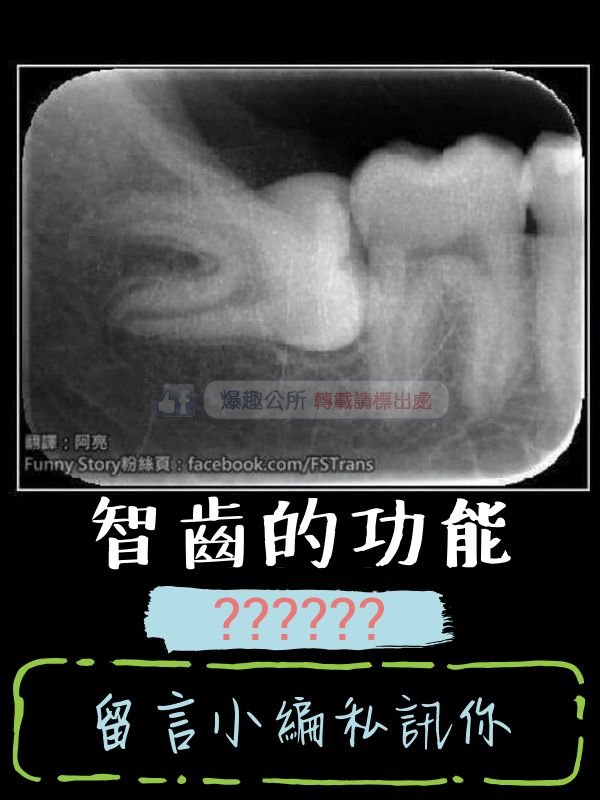

【迷你】破除百年來的大哉問 智齒存在的意義